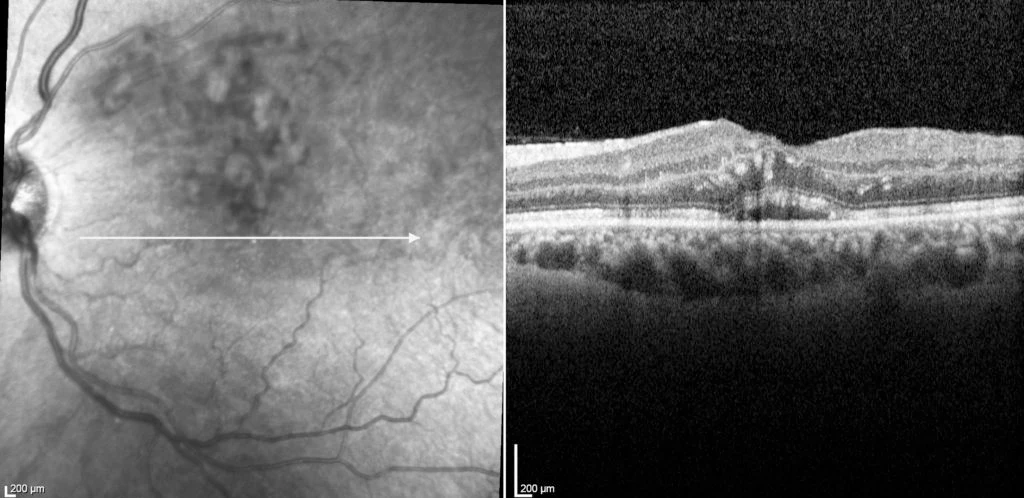

Treatment of intravitreal Lucentis injection therapy was instituted, and four weeks after the first injection his vision returned to 6/9 and his macular oedema dramatically improved, as seen in figure 2 below.

Figure 2